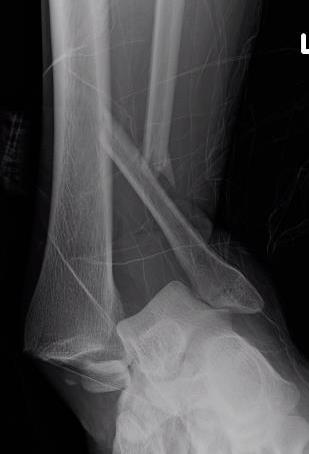

trimallTrimallTrimallTrimall

ankeankleankleankle